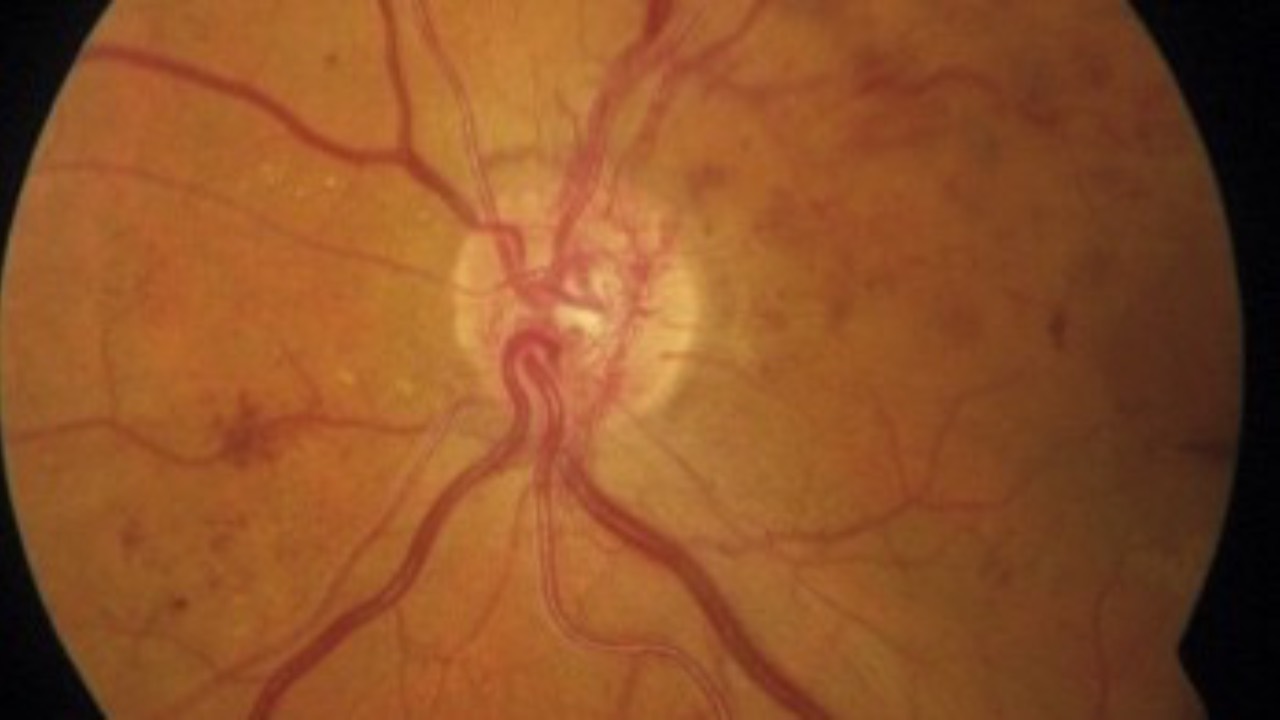

Diabetic Retinopathy Risks In Younger Age

The first three also matter...

Recent study findings have identified eight independent risk factors for diabetic retinopathy (DR) in younger and middle-aged individuals. Place of residence, education level, medical payment method, BMI, disease duration, hyperlipidemia, physical activity level, an...